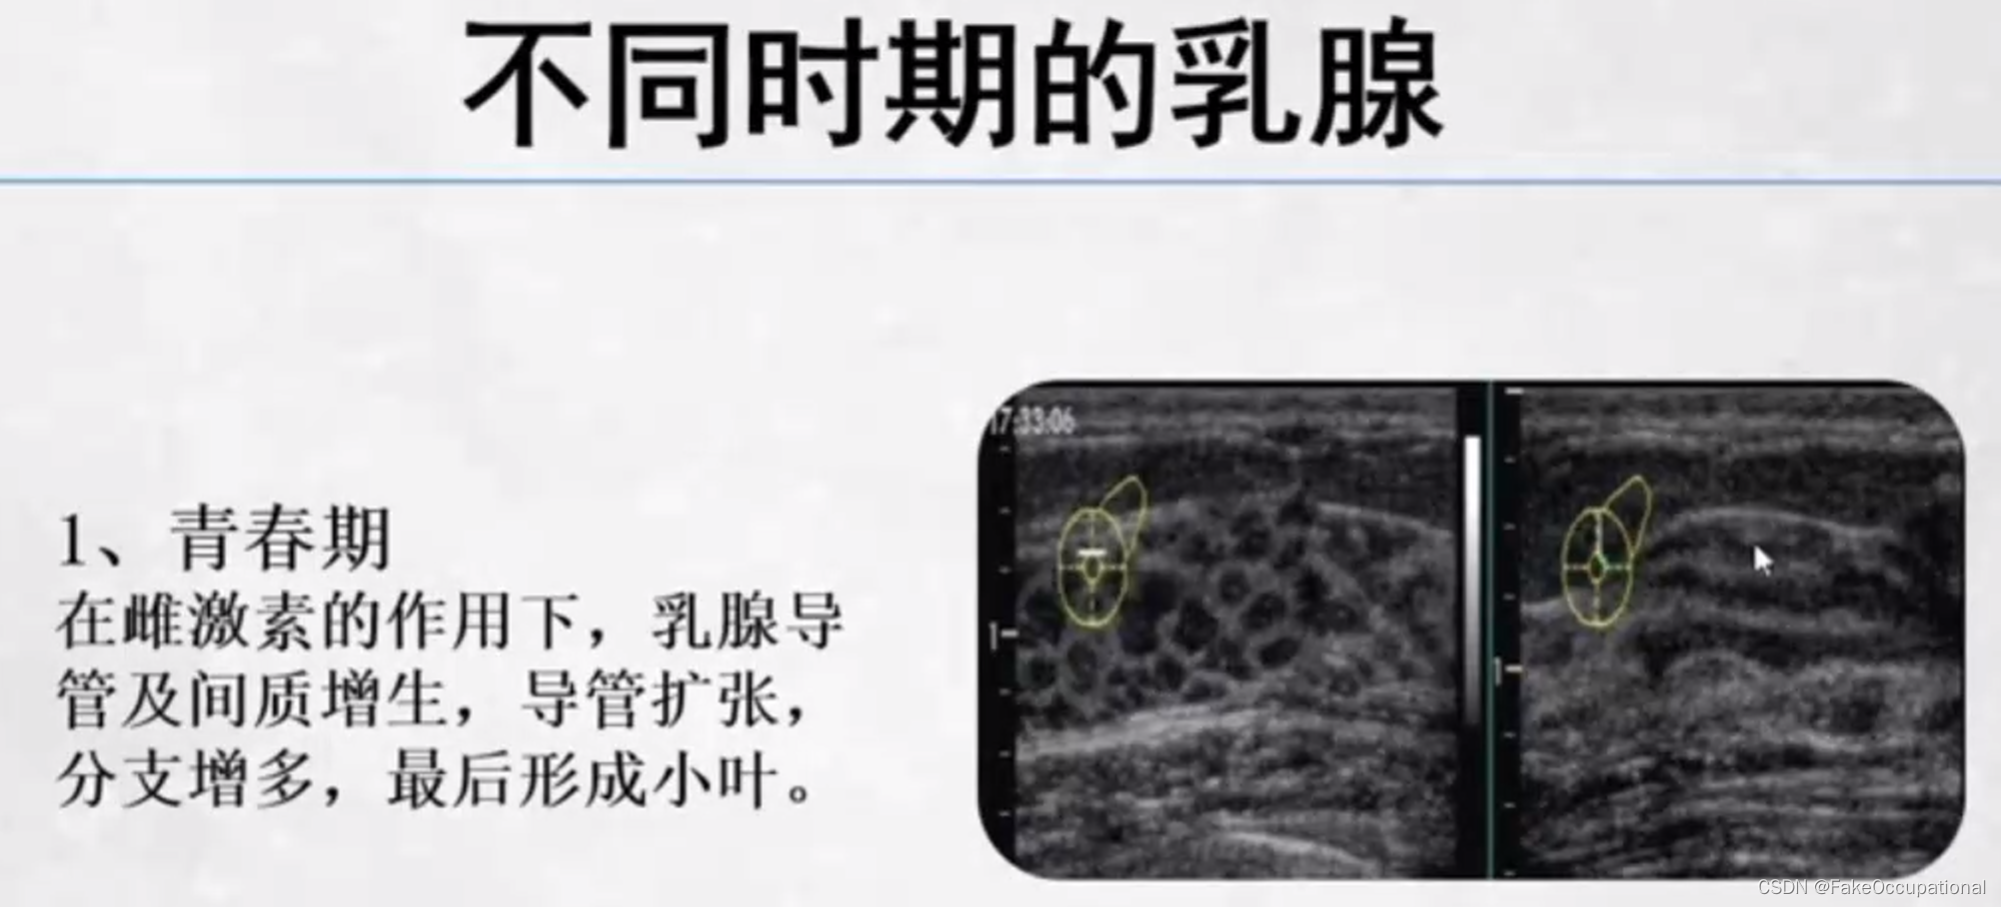

乳腺的生理解剖概要

乳腺的生理解剖概要